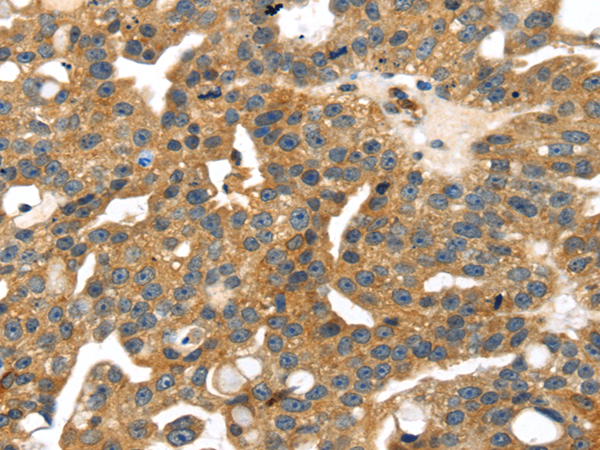

分类: 科研抗体货号: P08789别名: CEDNIK; SNAP-29应用: IHC反应种属: Human, Mouse, Rat